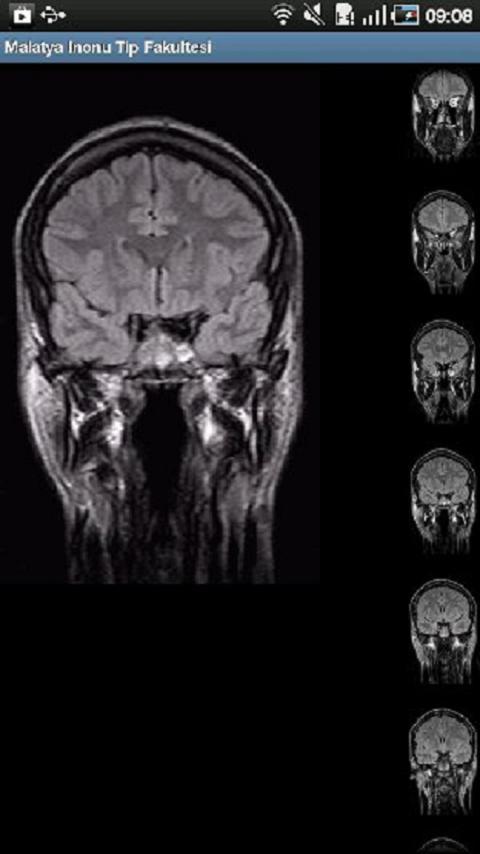

Ausgehandelte mobile Krankenhäuser sind für die Anmeldung des Krankenhauautomatisierungsantrags vorbereitet.

Es handelt sich um einen mobilen Antrag für mobile Krankenhäuser für vertragliche Krankenhäuser.